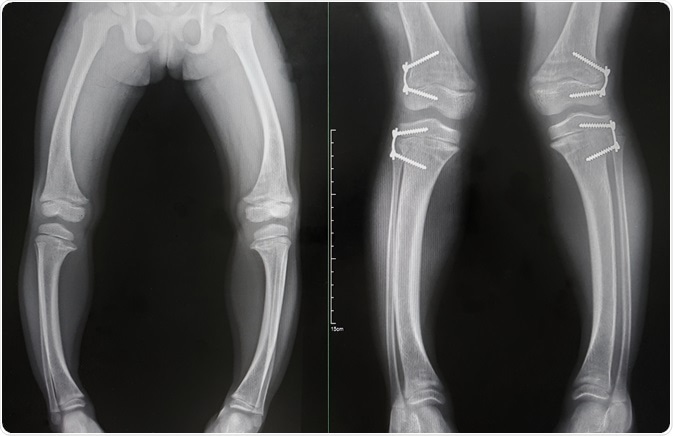

Rickets is defined as a condition associated with bone-deformity due to inadequate mineralization in growing bones. Albeit some cases are caused by renal disease, use of medication or specific hereditary syndromes, nutritional insufficiency is the most common cause of rickets, particularly in the developing world.

Rickets was initially reported in the mid-1600s when children who lived in polluted industrialized cities of northern Europe developed a severe bone-forming disease characterized by deformities and growth retardation. Glisson and his colleagues described typical findings of bone deformity with the curving of the legs.